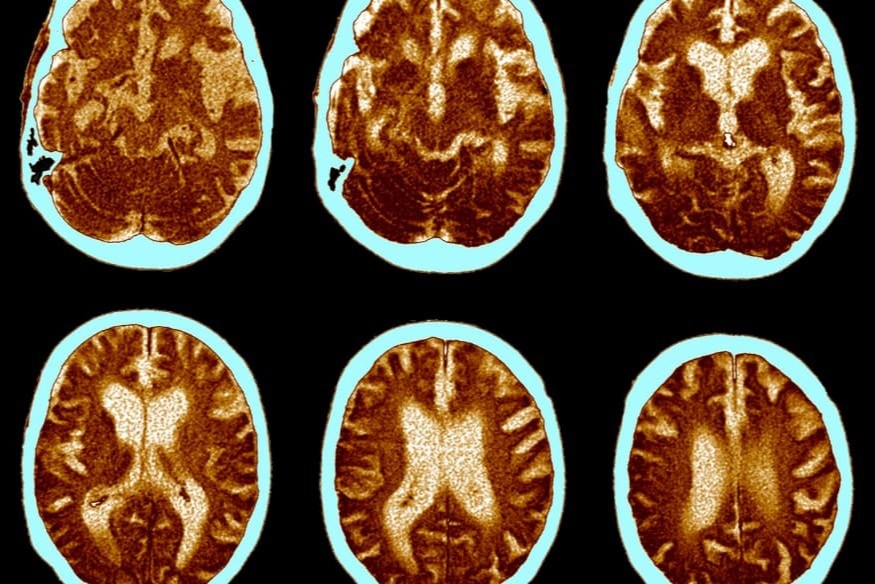

Une étude menée sur plus de 71 000 personnes montre qu’une carence en vitamine D à la naissance est liée à un risque accru de troubles mentaux ultérieurs, notamment la schizophrénie, l’autisme et le TDAH. Coordonnée par l’Université du Queensland et publiée dans The Lancet Psychiatry, l’étude repose sur les données de la cohorte danoise iPSYCH. Les chercheurs appellent à renforcer la supplémentation en vitamine D pendant la grossesse, à l’image de l’acide folique, pour prévenir les troubles neurodéveloppementaux.